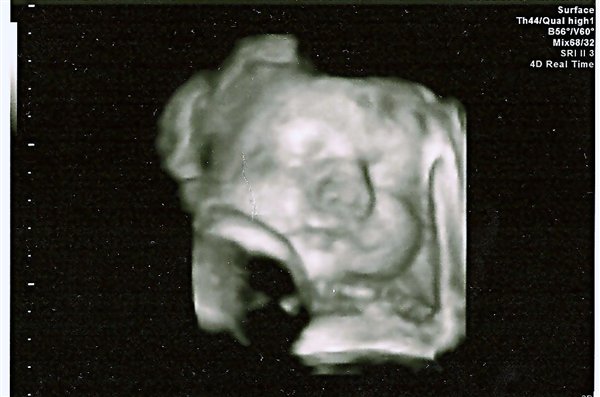

Min den første tog ca 30-40 min.. Men jo flere jeg fik jo kortere blev tiden Så den sidste tog 13-16 min, men jeg fik da et gratis 3D billed ud af det

Vedhæftede fotos (klik for at se i fuld størrelse)

Super dejligt billede )

Ej et dejligt billede. Er det taget til en almindelig NF?? På sygehuset

Nej det er taget til en almindelig scanning i uge 33.. Men på sygehuset ja..

På OUH har alle vist lige været på kursus, så jeg har været forsøgsdyr de sidste par gange...LÆKKERT